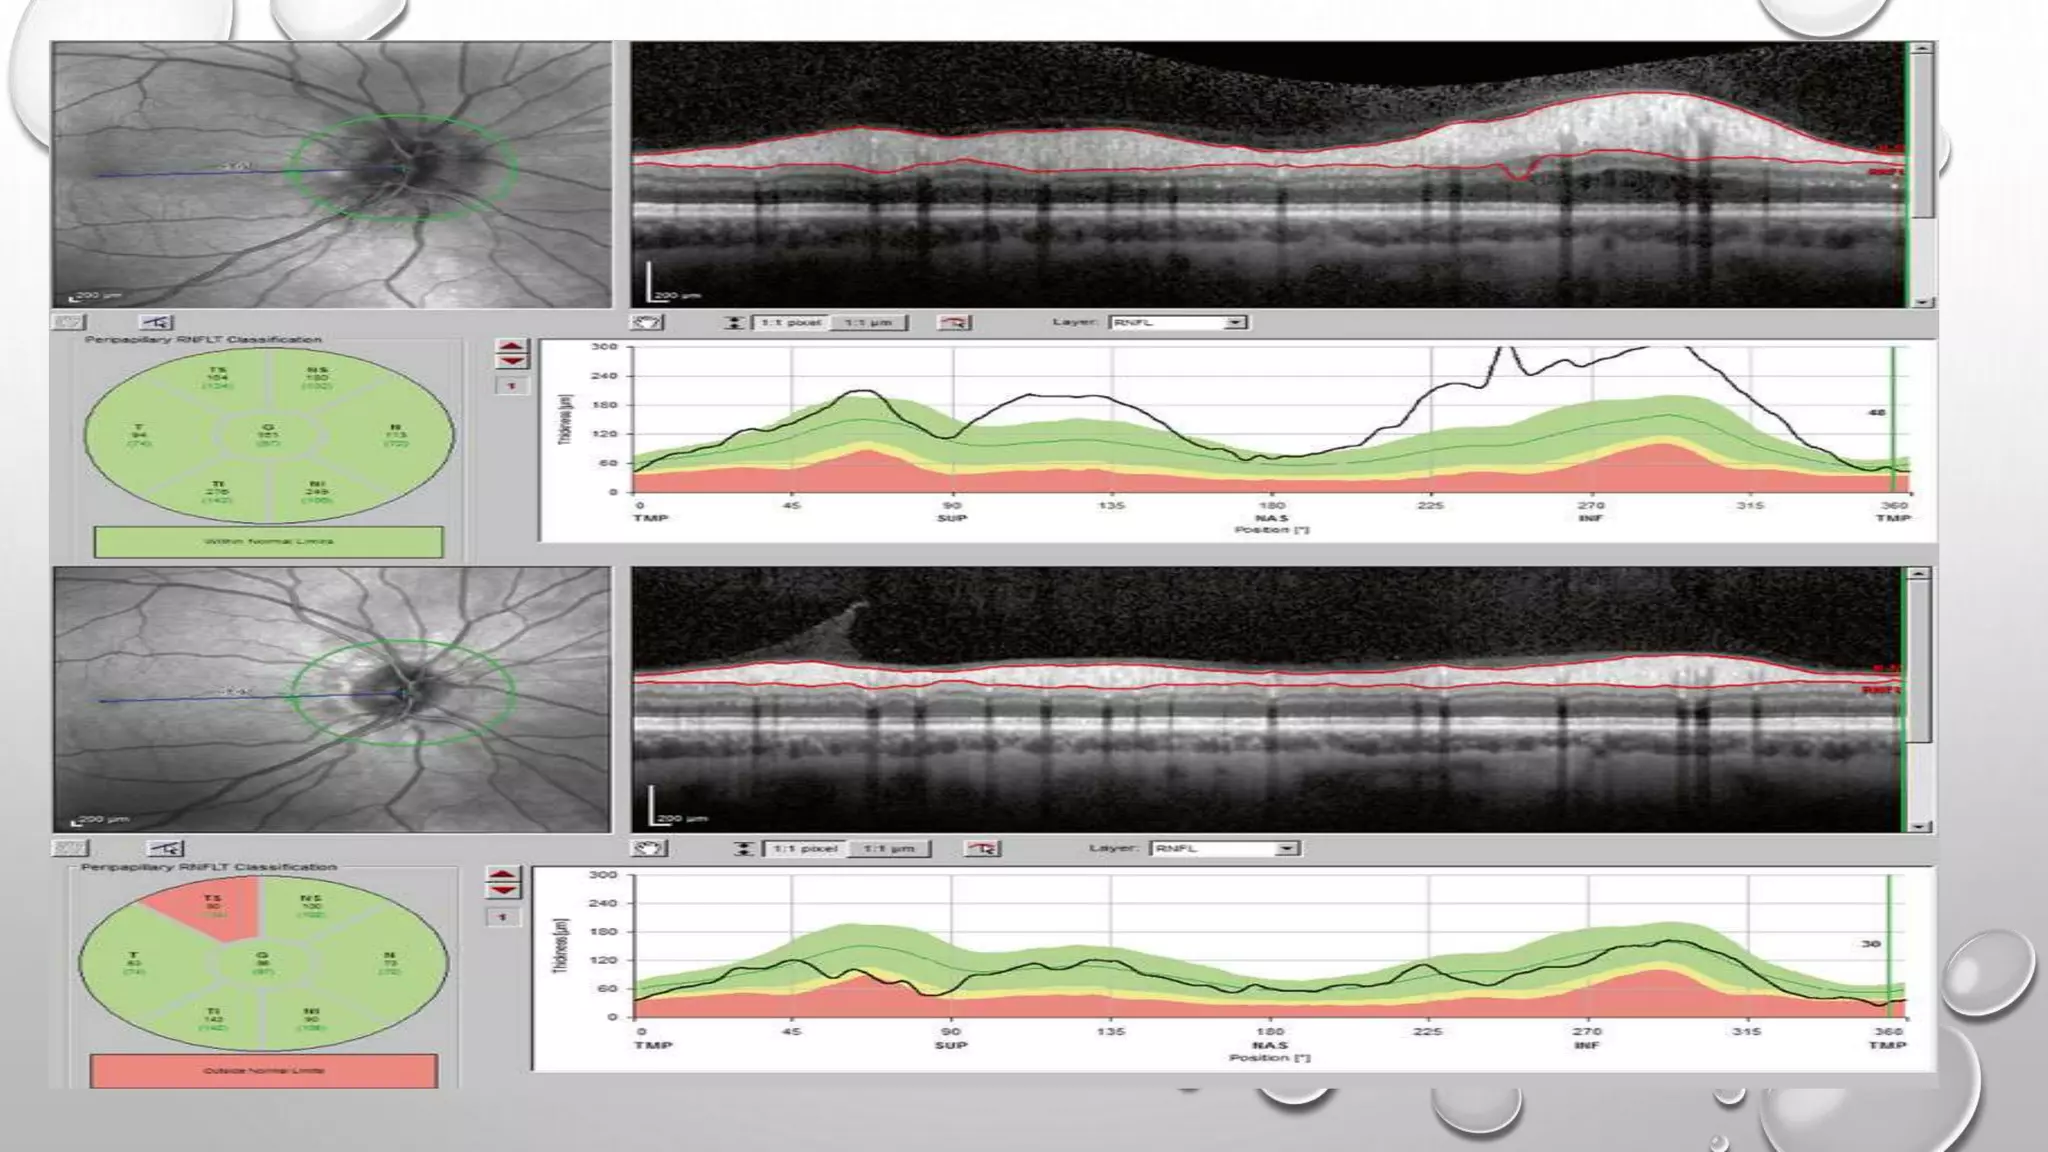

• All OCT studies have shown that mean peripapillary RNFL thickness is

decreased in MS patients compared to normal subjects.

• Greater RNFL thinning occurs in MS patients who are not treated with

immunomodulatory agents.

1- in MSON:

• The magnitude of RNFL atrophy is greater in the eyes with a history of prior

acute MSON; on average, the RNFL thins by about 20 % following an attack

of acute MSON.

• The majority of patients experience significant RNFL loss within 1 year after

an attack of acute MSON; most of this loss occurs within 3–6 months

• The earliest and most prominent RNFL loss occurs in the temporal quadrant,

corresponding with the fibers of the papillomacular bundle, which mediates central

vision “The diameter of axons in the PMB is only around 0.4 μm but up to 2.5 μm fibers

elsewhere in the retina.

• patients with clinically isolated syndrome (CIS) had the highest overall RNFL thickness

values (mean 87.8 μm), while patients with secondary progressive MS (SPMS) had the

greatest degree of thinning compared to control reference values (mean RNFL thickness

70.8 μm).